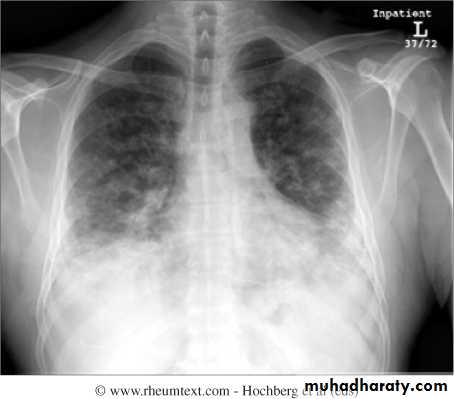

Interstitial lung disease occurs in up to 30% of patients and is strongly associated with the presence of antisynthetase (Jo1) antibodies.

Pulmonary –respiratory muscle weakness, aspiration, interstitial lung disease ,pulmonary hypertension and pulmonary vasculitis.Cardiac –heart block ,arrhythmias and cardiomyopathy.